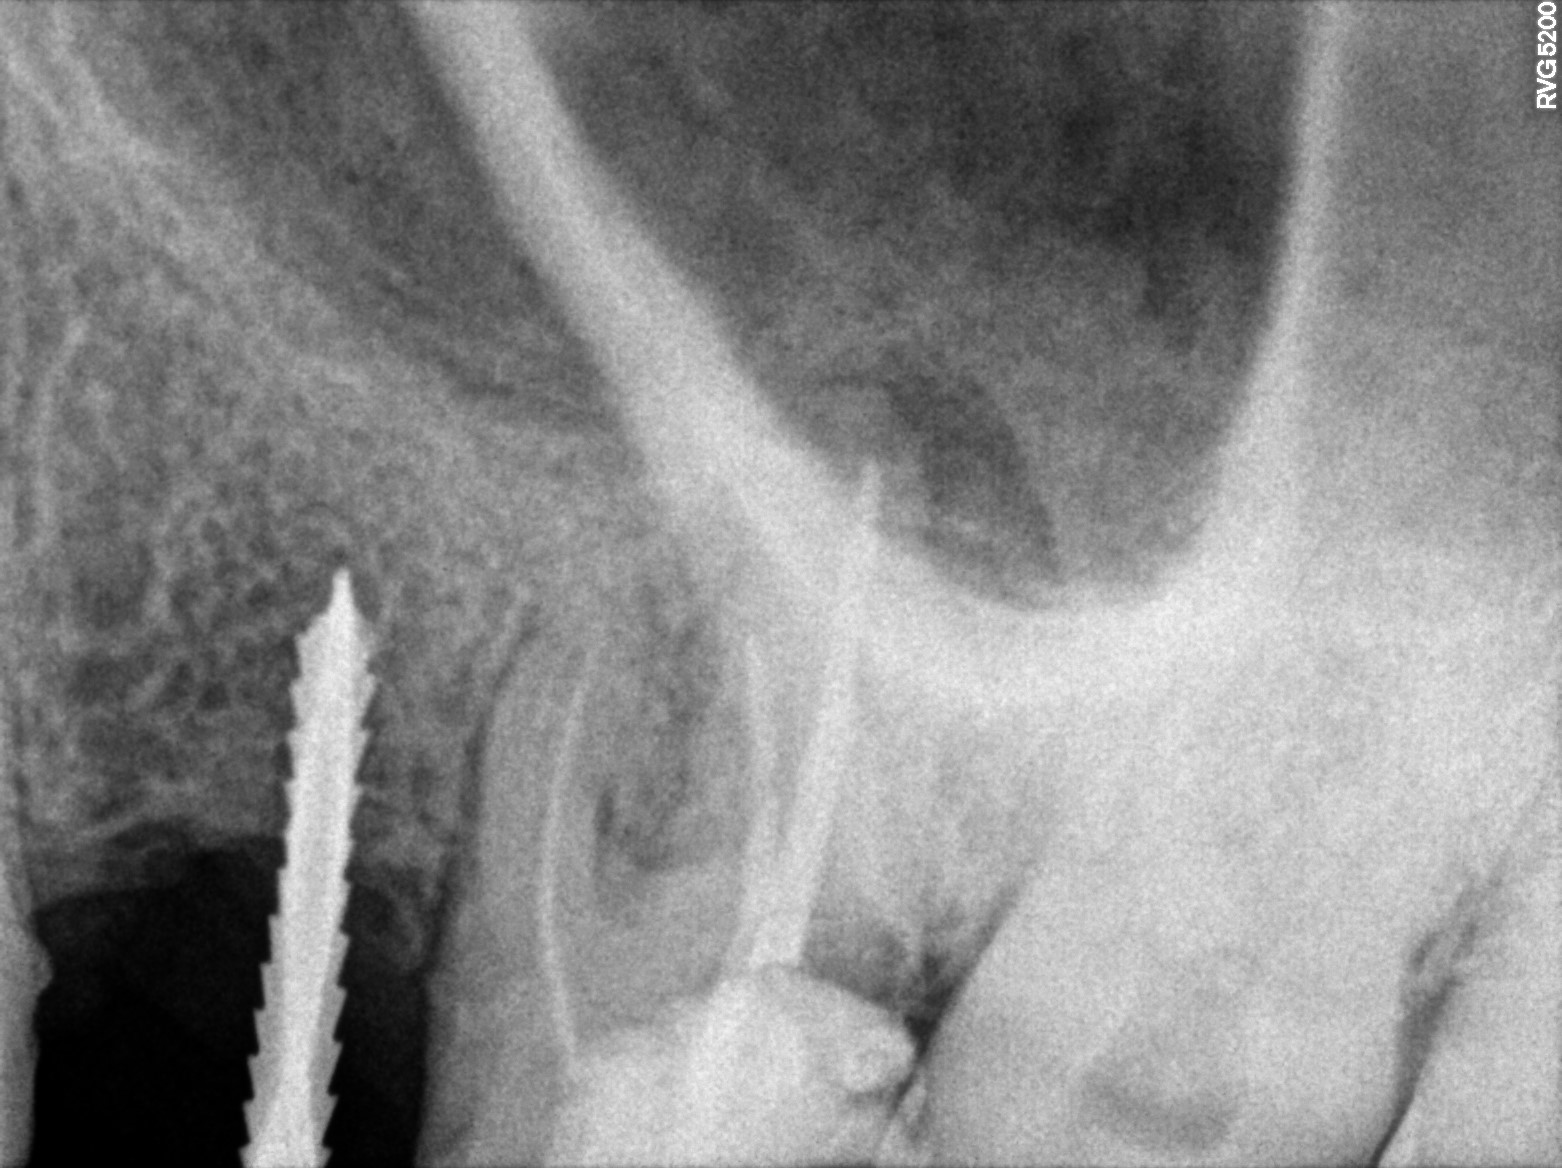

Dental Radiographs FHIR: DocumentReference · LOINC 24641-7

R55.jpg

24641-7